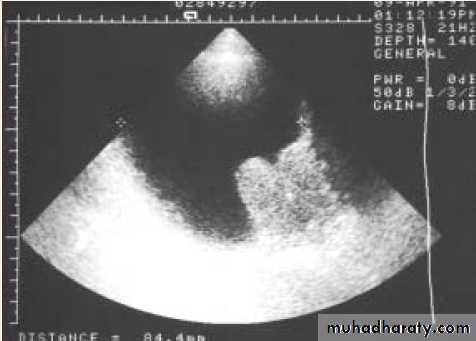

INVESTIGATIONS

Optional

• U/S.